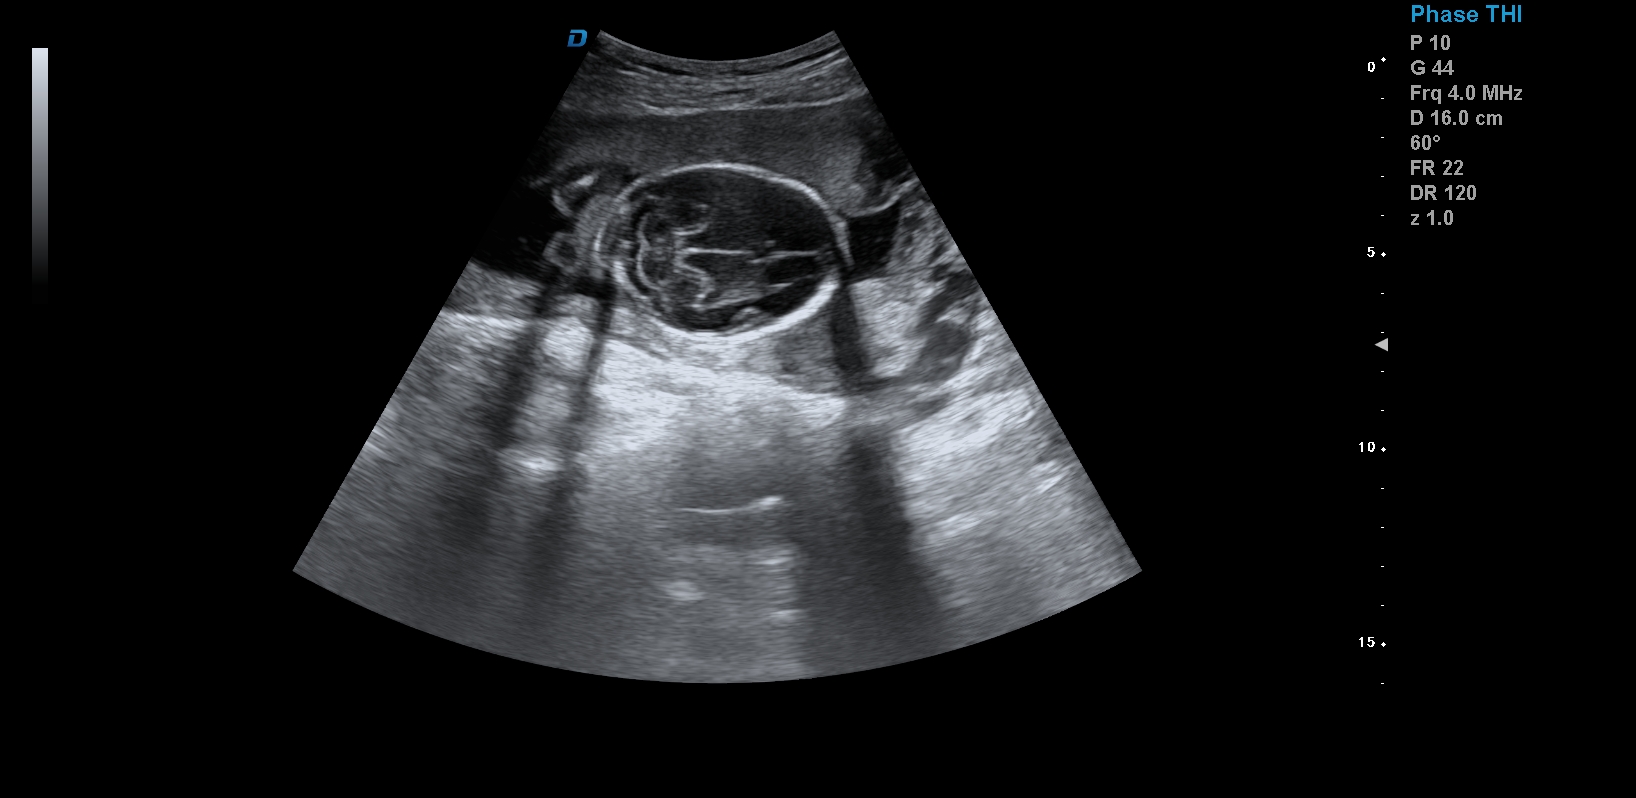

四維彩超,見證生命最初的感動

醫用四維彩超機作用

首先,四維彩超檢查是采用高清晰度的彩超儀對胎兒進行各個心臟器官及組織的一次全面檢查,可以立體顯示胎兒的發育情況,胎兒在子宮內的任何狀態都可以觀察到。對胎兒畸形能夠早診斷,及時地做出相應的措施,以達到優生優育的標準。

四維彩超不但成像清晰,更是在三維的基礎之上附加時間這個矢量。這就在排畸的同時能時刻觀察寶寶在宮內的一舉一動,吃手指、打哈欠、吮吸……寶寶在宮內憨態可掬,讓孕媽媽母愛井噴,幸福不已。這也是孕媽媽們選擇四維的主要原因,試想,誰不想在辛苦懷孕期間提前看一看自己寶寶的模樣呢?

1、四維彩超是目前先進的彩色超聲技術.能直觀立體現實人體器官動靜態三維結構,一定程度上提高臨床診斷的準確性。

3、清晰成像:采用先進的超聲成像技術,擁有高清晰,高分辨率、高精確度優點,能清晰看到包括生殖器、內臟器官在內的胎兒的各個部位發育情況.

四維彩超臨床圖